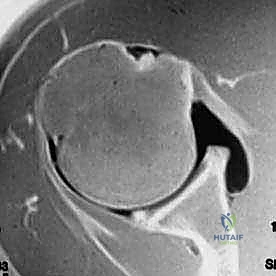

* التصوير بالرنين المغناطيسي (MRI): هو المعيار الذهبي للتشخيص. يوفر صوراً تفصيلية ثلاثية الأبعاد تظهر بدقة متناهية درجة الالتهاب، سماكة الوتر، وجود تمزقات جزئية، وحالة الأنسجة المحيطة مثل الكفة المدورة والشفا الحقاني.